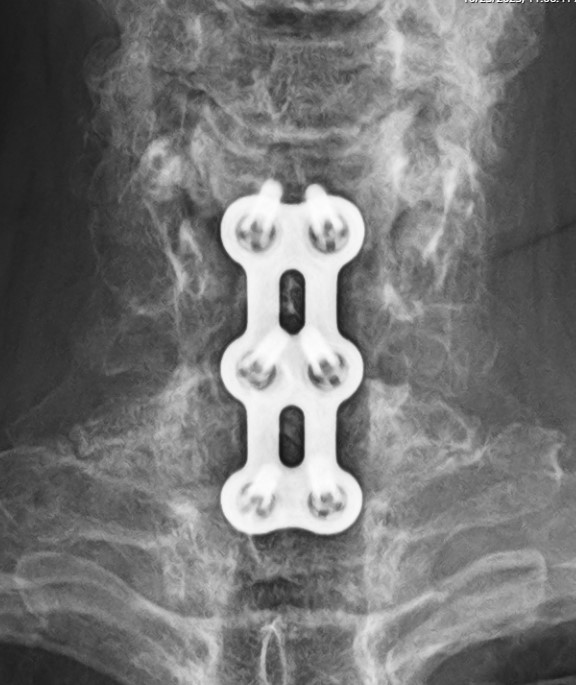

Reflex Hybrid Anterior Cervical Plate

COMPANY: Stryker-K2M

The Reflex Hybrid Anterior cervical plate system by Stryker is an ACDF plate from 1 to 4 levels. The plate has automatic locking screws and has self drilling or self tapping screws